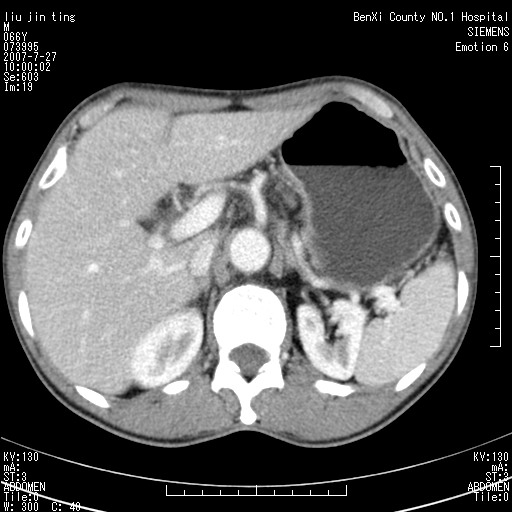

腹痛,背痛,无恶心呕吐,不黄,彩超示胰腺钩癌,ct扫描病灶平扫30-40hu,增强后动脉期40--60hu,静脉期50-68hu,真的是钩突上的么?您要试一试么?

静脉期

沿着肠系膜上动脉呈匍匐性生长的软组织肿块,形态不规则,包绕肠系膜上动脉,呈明显强化,考虑来源于肠系膜的恶性肿瘤

沿着肠系膜上动脉呈匍匐性生长的软组织肿块,形态不规则,包绕肠系膜上动脉,呈轻-中度强化,考虑来源于肠系膜的恶性肿瘤。

钩突是正常的,只见腹膜后淋巴结的肿大,考虑淋巴瘤或转移可能。